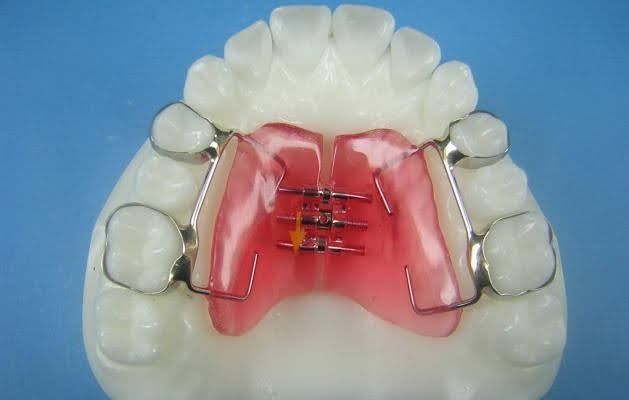

RAPID MAXILLARY EXPANSION

TYPES OF RME APPLIANCES:

Derichsweiler type:

• The first premolars and the first molars are banded.

• Wire tags are soldered onto the palatal aspect of the bands.

• These wire tags get inserted into a split palatal acrylic plate incorporating a screw at its centre.